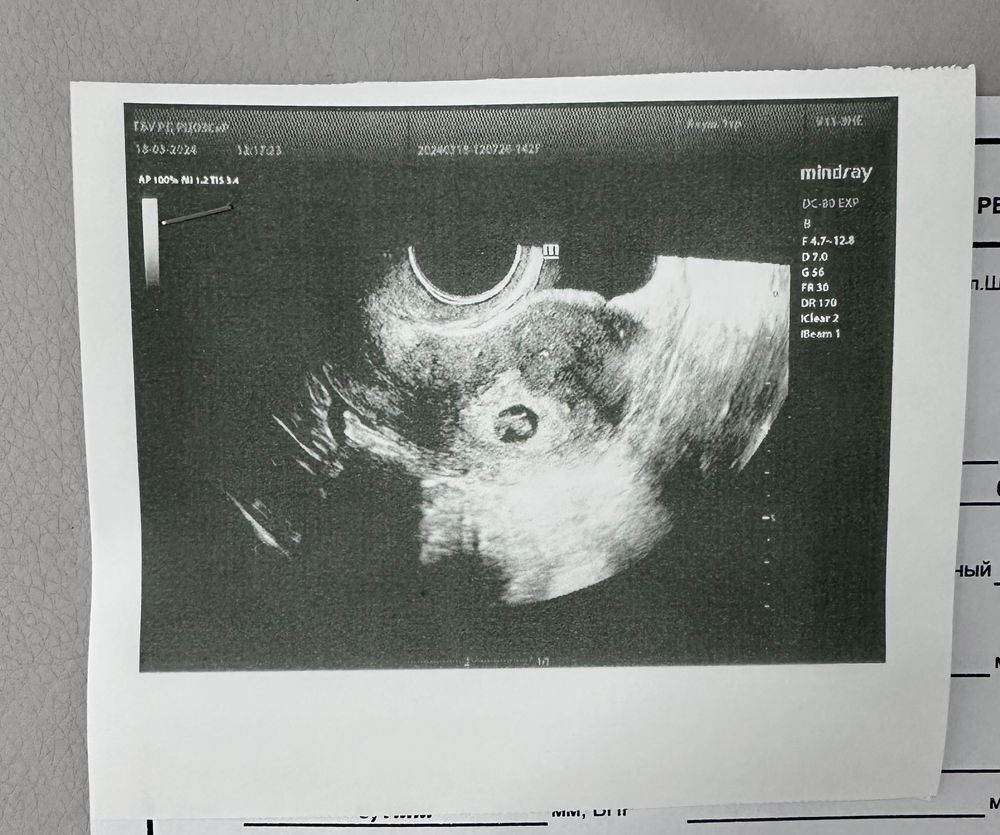

30дпп узи🌺

18.03.2024